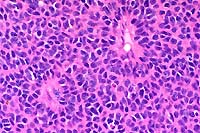

obj

- Case 12-2. Lymph node. Multifocally within zones suppuration

and necrosis, are multiple large colonies of bacteria.

- AFIP Diagnosis: Lymph node: Lymphadenitis, necrotizing,

suppurative, diffuse, severe, with numerous bacilli, Siberian

polecat x black-footed ferret (Mustela eversmanni x M. nigripes),

mustelid.

- Note: Necrosis, suppurative inflammation and hemorrhage

are present within the surrounding perinodal tissues in some

sections.